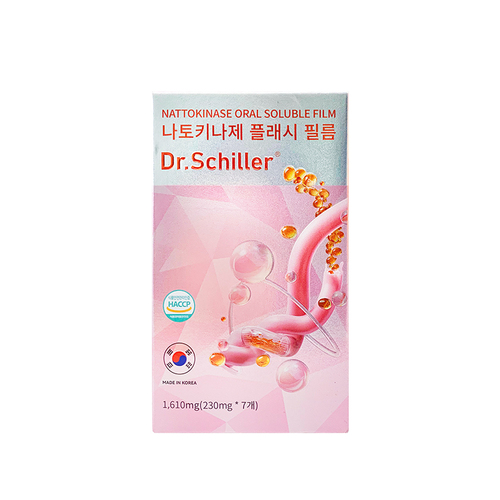

Dr.Schiller는 세계 최고의 과학 연구팀이 공동으로 만든 새로운 건강 관리 브랜드입니다. 우리는 소비자의 실제 요구에서 출발하여 개인화된 건강 솔루션을 제공합니다! 제품은 건강 관리, 구강 미용, 개인 관리 등 트랙을 포함합니다. '동결 건조 플래시 방출 특허 기술'을 핵심으로, 모든 제품이 신속하고 완전하게 천연 활성 성분을 방출하여 소비자가 순수하고 효율적인 체험을 할 수 있도록 합니다. 의 피부 관리 또는 건강 효과.

FDF 동결 건조 기술(특허 번호: ZL201210572660.8): 3초 동안 활성 세포를 -196°까지 신속하게 냉동하여 '휴면'하게 하여 유효성분의 활성과 안정성을 극대화할 수 있습니다.

RWD 플래시 기술(특허 번호: 201410187485. X): 효능 성분의 생체 활성을 잘 보존하여 ‘효율 잠금’을 실현할 수 있다.